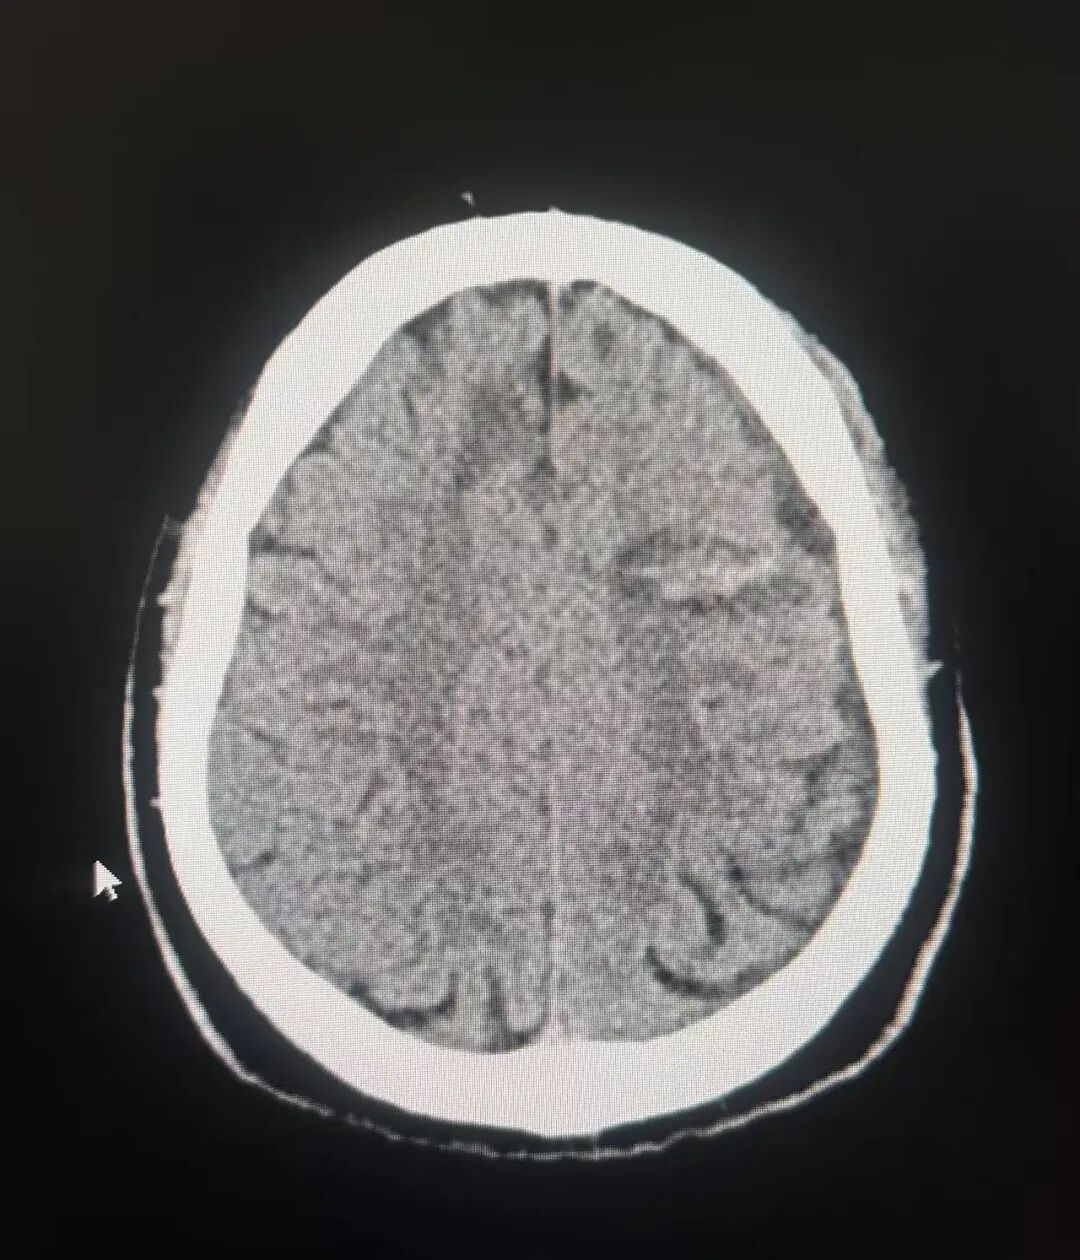

在手术室内,孙康健主任团队在神经外科机器人辅助下为患者植入了多个电极,后在脑电监测下通过检查及电刺激的方式确定了患者的致痫灶位于左侧额叶靠近功能区处,确定位置后为患者进行了二次的立体定向脑电图毁损治疗。现患者恢复良好,手术后癫痫无发作。

PET和核磁共振融合确定致痫灶

毁损致痫灶